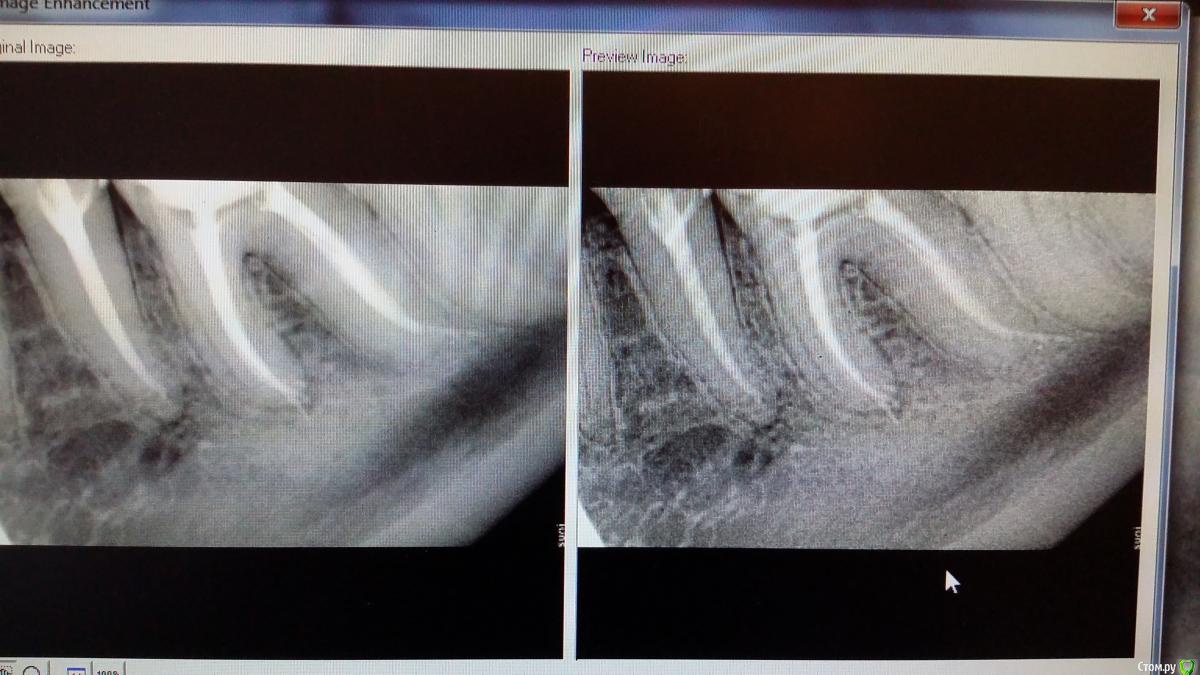

Recive Опубликовано 16 февраля, 2015 Автор Поделиться Опубликовано 16 февраля, 2015 Там была ступенька в дистальном канале ((( Не много вывел , при конденсации, силлера. 1 Ссылка на комментарий

Recive Опубликовано 16 февраля, 2015 Автор Поделиться Опубликовано 16 февраля, 2015 Нужно. Снимок после пломбировки покажитеснимок просили. Ссылка на комментарий

Л Ю С Я Опубликовано 16 февраля, 2015 Поделиться Опубликовано 16 февраля, 2015 снимок просили.По Вашему мнению что в дистальном за апексом? Ссылка на комментарий

Recive Опубликовано 17 февраля, 2015 Автор Поделиться Опубликовано 17 февраля, 2015 По Вашему мнению что в дистальном за апексом?Там была ступенька в дистальном канале ((( Не много вывел , при конденсации, силлера. Ссылка на комментарий

Л Ю С Я Опубликовано 17 февраля, 2015 Поделиться Опубликовано 17 февраля, 2015 Ступеньку желательно обойти . Хотя дольше похоже на боковое отверстие имхо Ссылка на комментарий

Recive Опубликовано 17 февраля, 2015 Автор Поделиться Опубликовано 17 февраля, 2015 Ступеньку желательно обойти . Хотя дольше похоже на боковое отверстие имхо.04 протейпер f1 yellow Зуб не болел и никак не проявлял себя. Принято решение заплозапломбировать.собственно фото каналов после абтурации.скажите пожалуйста, а медиальные каналы по апексу нормально? Очень редко получается 1мм не проталкивать за апекс. Хотя по контрольной рентгенограмме с мастер-шмастер-штифтом все чики-пуки. Ссылка на комментарий

Л Ю С Я Опубликовано 17 февраля, 2015 Поделиться Опубликовано 17 февраля, 2015 Если стоп упор сформирован , апекс не на дырявите, мастер штифт правильно подобран,ничего не должно при латералке выводится. Может силера много берете, выбор спредера, как давите и др- все имеет значение. Соблюдайте РД , несколько раз перемеривайте Ссылка на комментарий